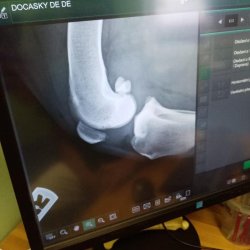

Mia s utrženými předními křížovými vazy

Mia je třicetisedmi kilogramová kříženka rotvajlera přijatá do Dočasek DeDe. Mia podstoupila kastraci a ve spojitosti s jejím horším sedáním a vstáváním bylo panem veterinářem provedeno vyšetření a byla diagnostikována dysplazie kyčelních kloubů, ale bohužel také utržení obou předních křížových vazů. Jistě tím Mia trpí již dlouho, s chůzí nemá žádný problém, nicméně kolénka má oteklá. A tak musí tato rotvajleří slečna zhubnout a podstoupit operaci křížových vazů na obou nohách. Mia shání novou dočasnou péči i případnou adopci.

Tety z Dočasek nyní shánějí penízky na úhradu operací kolen Mii, kdy jedno koleno, metodou TTA nebo CWO, vyjde na 20 000 Kč, tedy 40 000 Kč za obě kolena. Na operace Mii vyhlásily sbírku s názvem "Kolena Mia".